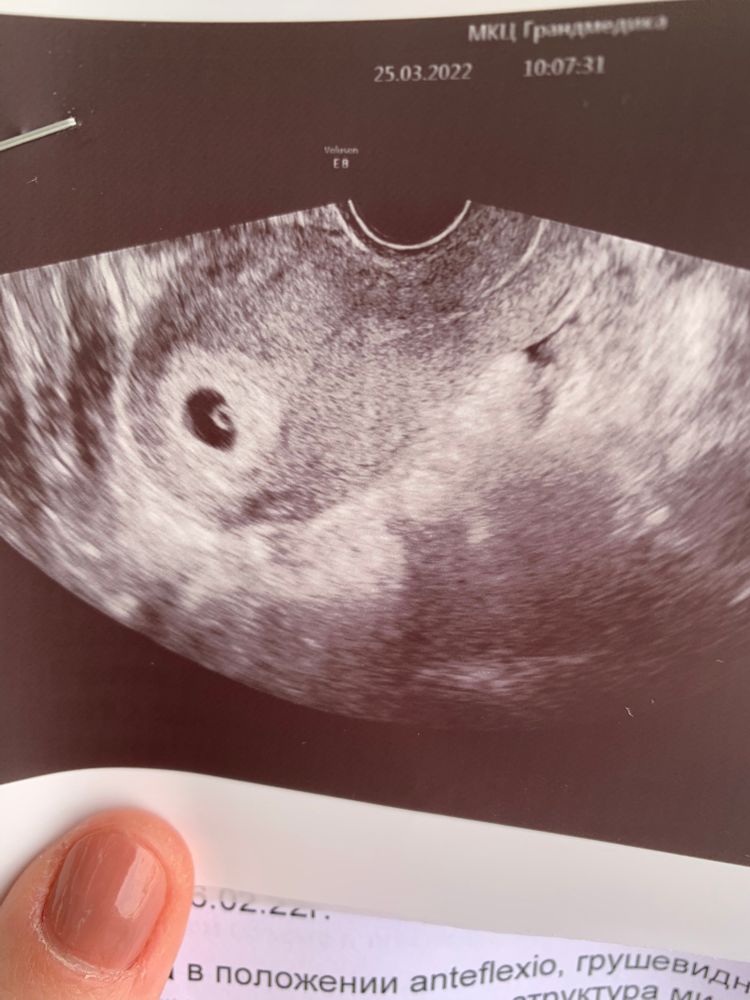

Беременность начала безответственно. ХГЧ в динамике не проследила (гемотест далеко, а сдавать в другой лаборатории - только трепать себе нервы, все ли правильно и адекватно с учётом разных методик и шкал). Только сама себе назначила начинать пить фолиевую и записалась на УЗИ.

УЗИ заставило понервничать. Тыц-тыц датчиком, «одевайтесь, сейчас все опишу» холодным голосом. И только от сухого «Сердцебиение: +» в выписке отлегло. Отстаёт на 3 дня от срока, высчитанного по менструации, но пока все в порядке.

Ну привет, человек <3